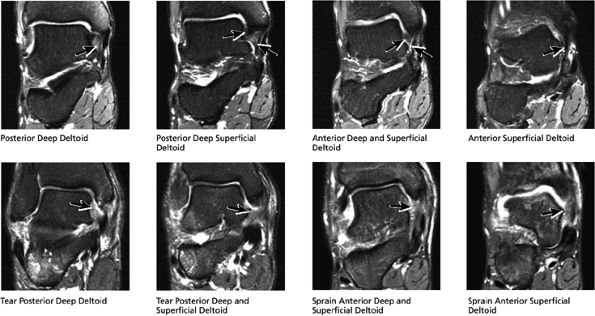

The deltoid ligament consists of superficial and deep layers.

fascicle inserts onto the superior border of the calcaneona vicular ligament. The deep part of the deltoid, which is rectangular, consists of a small anterior component (the anterior tibiotalar ligament) and a strong posterior component (the posterior tibiotalar ligament) (Fig. 5.64). The posterior tibiotalar ligament represents the strongest part of the entire medial ligament complex. The deep portion of the deltoid ligament, covered by synovium, is intra-articular.